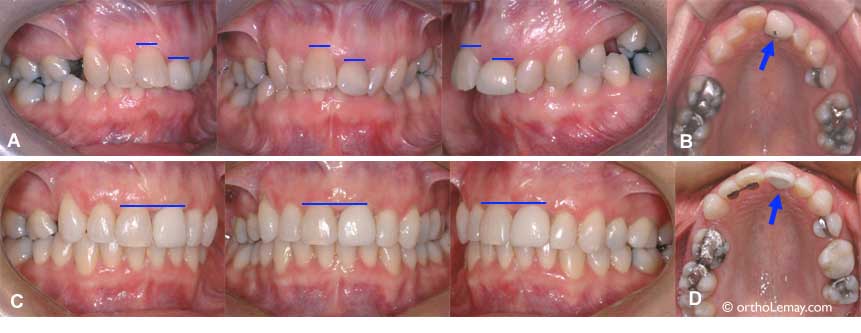

(A et B) La centrale supérieure gauche de cette femme de 43 ans est plus courte et plus basse que celle de droite et le contour de la gencive est très inégal et inesthétique. De plus, elle a une couronne épaisse qui visait à camoufler une rotation importante. (flèche bleue). (C et D) Après l’orthodontie, la position des incisives fut corrigée de façon à harmoniser le niveau de la gencive et permettre au dentiste généraliste de faire une nouvelle couronne mieux proportionnée et plus esthétique.

Mouvements orthodontiques pour harmoniser des incisives de longueur inégale et le niveau de gencive

Utilisation de mouvements orthodontiques pour harmoniser le niveau de gencive des centrales et permettre au dentiste de faire une restauration plus esthétique après le traitement d’orthodontie.